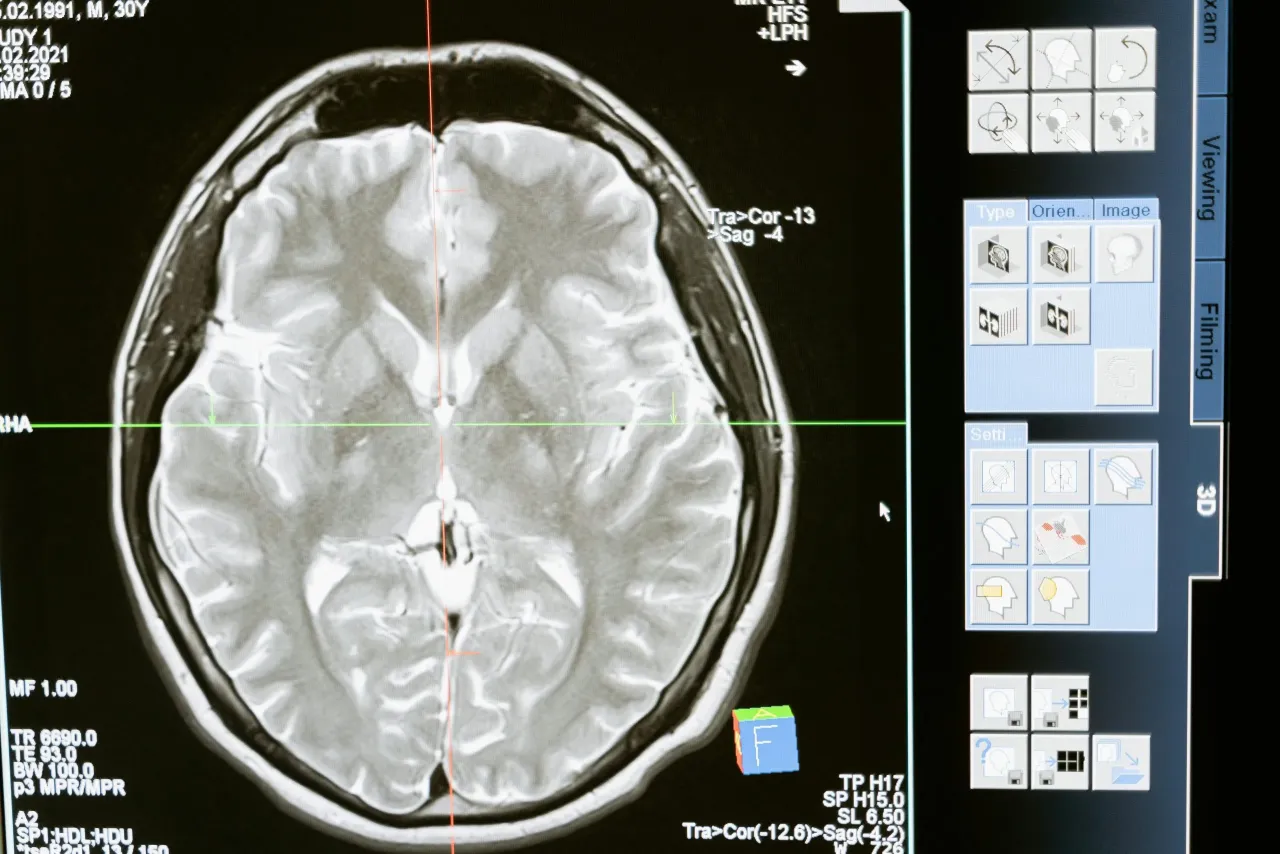

Środek kontrastowy, najczęściej na bazie gadolinu, to specjalna substancja podawana dożylnie przed lub w trakcie badania rezonansem magnetycznym. Jego głównym zadaniem jest poprawa widoczności i kontrastu między różnymi tkankami i strukturami w organizmie, co pozwala na dokładniejszą diagnostykę. Dzięki niemu lekarz radiolog może lepiej ocenić zmiany patologiczne, takie jak guzy, stany zapalne czy uszkodzenia naczyń krwionośnych. Po spełnieniu swojej funkcji w organizmie, gadolin jest traktowany jako substancja obca i musi zostać wydalony. Ten proces odbywa się głównie przez nerki. Są one odpowiedzialne za filtrowanie krwi i usuwanie z niej zbędnych produktów przemiany materii oraz substancji obcych. Aby proces ten przebiegał sprawnie i bezpiecznie, nerki muszą funkcjonować prawidłowo.